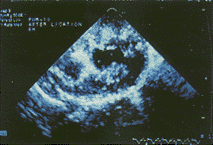

急性缺血心肌 8条犬冠脉结扎后6小时均获满意的DPTI、MCE显示,左室短轴切面上24个区域心肌运动消失,DPTI呈现紫黑色,MCE显示的充盈缺损区,和正常心肌间有明显的分界,能明确地测量缺血区的面积等各项指标(图1~2)。

图1 DPTI显示冠脉结扎后6小时无心肌运动呈现紫黑色

图2 MCE显示冠脉结扎后6小时造影充盈缺损区